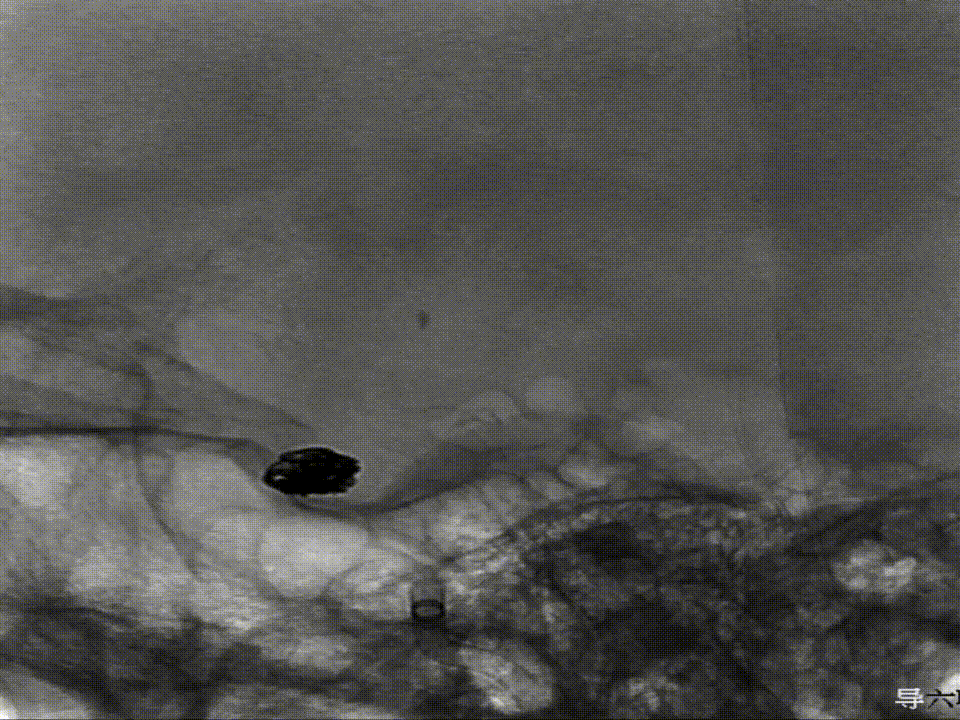

璞慧 0.017微导管塑形

Asahi 0.014微导丝塑形后辅助Echelon 10微导管进入A2远端备支架释放。

Asahi 0.014微导丝导引璞慧 0.017微导管进入动脉瘤内。

通过璞慧0.017微导管填入Target 1.5/2弹簧圈部分成篮,后释放Atlas 3.0/15支架覆盖瘤颈处,继续填入弹簧圈时微导管脱出,尝试用弹簧圈将微导管引导超选瘤腔失败。

撤出弹簧圈,Asahi 0.014微导丝引导璞慧 0.017微导管穿支架网孔进入动脉瘤内。

继续填入Target 1.5/2弹簧圈成篮,后完全释放支架,其近端位于颈内动脉分叉处,远端位于A1远端。

填入第一枚弹簧圈

通过调整栓塞微导管的张力继续填入Target 1/3弹簧圈。